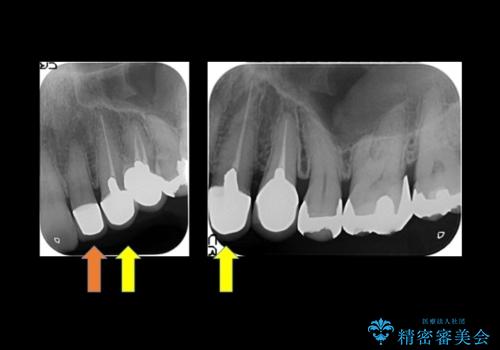

- 左上の前歯が小さく左右対称ではないのと、保険の前歯の被せ物のやりかえを希望して来院。

被せ物だけやりかえており、患者様のご希望もあり、根の治療や土台(コア)のやりかえは行なっていません。